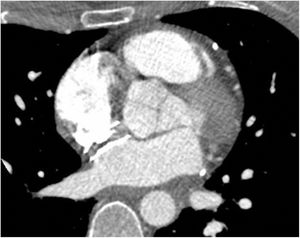

Caso clínico 3Por último, se describe el caso de una mujer de 40 años, con antecedente de ictus isquémico hacía dos años, sin secuelas, siendo diagnosticada de FOP y realizándose su cierre por vía percutánea venosa femoral con dispositivo de 24 mm. Presentó dolor torácico opresivo asociado a disnea, junto con hipotensión, evidenciándose en la ecocardiografía taponamiento cardiaco, que requirió pericardiocentesis con salida de unos 250 mL de contenido hemático. Se completó el estudio con tomografía computarizada, que objetivaba la aorta de calibre normal y descartaba síndrome aórtico agudo. El dispositivo de cierre de FOP contactaba íntimamente, a 1-2 mm, con la pared aórtica, con el techo de la aurícula izquierda y la entrada de la vena cava superior a la aurícula derecha, pero sin identificar claramente punto de solución de continuidad de la pared cardiaca (fig. 3). También se realizó ecocardiografía transesofágica, con ausencia de flujo a través del dispositivo o cámaras cardiacas. Tras discutir el caso en sesión multidisciplinar, se decidió retirada quirúrgica del dispositivo de cierre de FOP. No se encontró zona sangrante de las cavidades cardiacas, pero sí se habían establecido adherencias en el techo de la aurícula izquierda como consecuencia de posible erosión de la misma por el dispositivo. Se retiró el dispositivo y se realizó la reconstrucción del septo interauricular con parche de pericardio heterólogo. La evolución postoperatoria transcurrió sin incidencias.

Tomografía computarizada preoperatoria tras drenaje del derrame pericárdico. El dispositivo de cierre de FOP contacta íntimamente, a 1-2 mm, con la pared aórtica, con el techo de la aurícula izquierda y la entrada de la vena cava superior a la aurícula derecha, pero sin identificar claramente punto de solución de continuidad de la pared cardiaca.